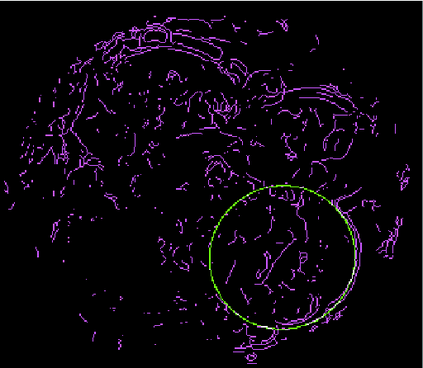

We present a novel method for identification of the boundary of embryonic cells (blastomeres) in Hoffman Modulation Contrast (HMC) microscopic images that are taken between day one to day three. Identification of boundaries of blastomeres is a challenging task, especially in the cases containing four or more cells. This is because these cells are bundled up tightly inside an embryo's membrane and any 2D image projection of such 3D embryo includes cell overlaps, occlusions, and projection ambiguities. Moreover, human embryos include fragmentation, which does not conform to any specific patterns or shape. Here we developed a model-based iterative approach, in which blastomeres are modeled as ellipses that conform to the local image features, such as edges and normals. In an iterative process, each image feature contributes only to one candidate and is removed upon being associated to a model candidate. We have tested the proposed algorithm on an image dataset comprising of 468 human embryos obtained from different sources. An overall Precision, Sensitivity and Overall Quality (OQ) of 92%, 88% and 83% are achieved.